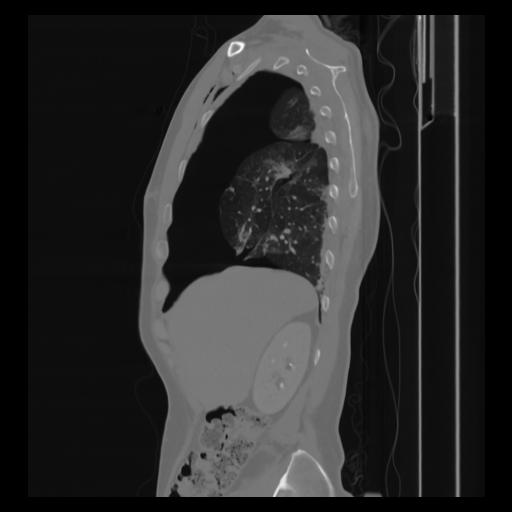

30 CUERPO,CE,Sagittal,3.000,CUERPO,Sagittal,